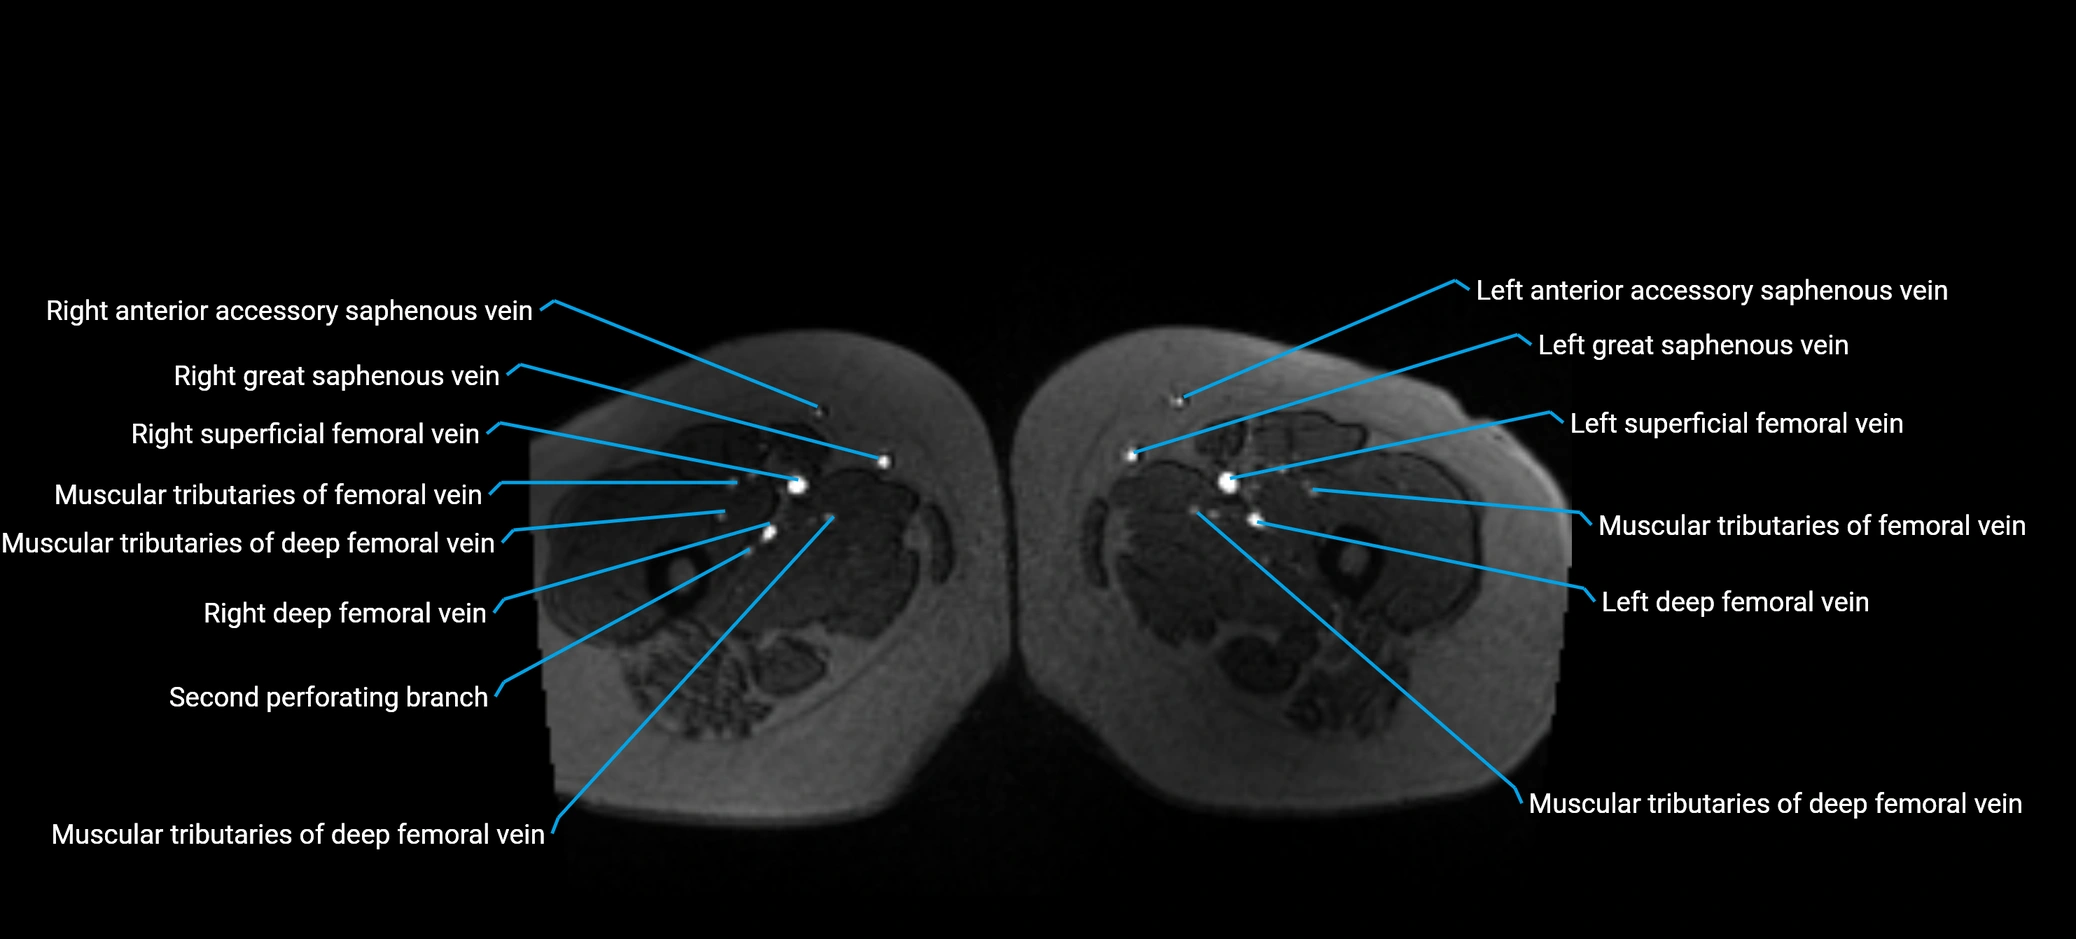

MRI image

image